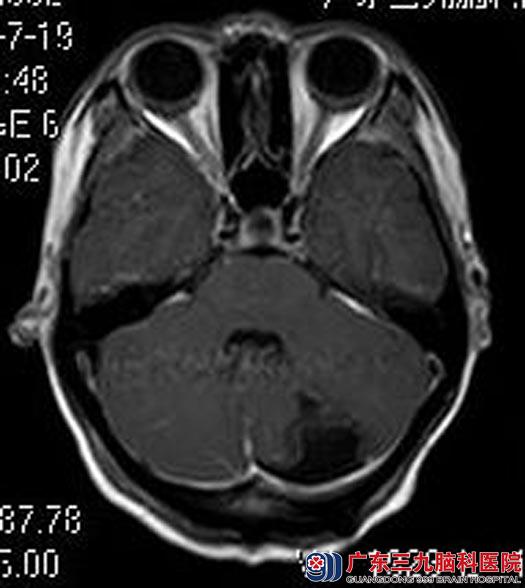

完善相关检查后,鲁明主任主刀,在全麻下行左侧小脑占位切除术,术中显微镜下见肿瘤呈红色,血供丰富,予镜下全切。术后徐小姐康复很快,已顺利出院。术后病理结果:间变型星型细胞瘤(WHO I级)。

▲手术后